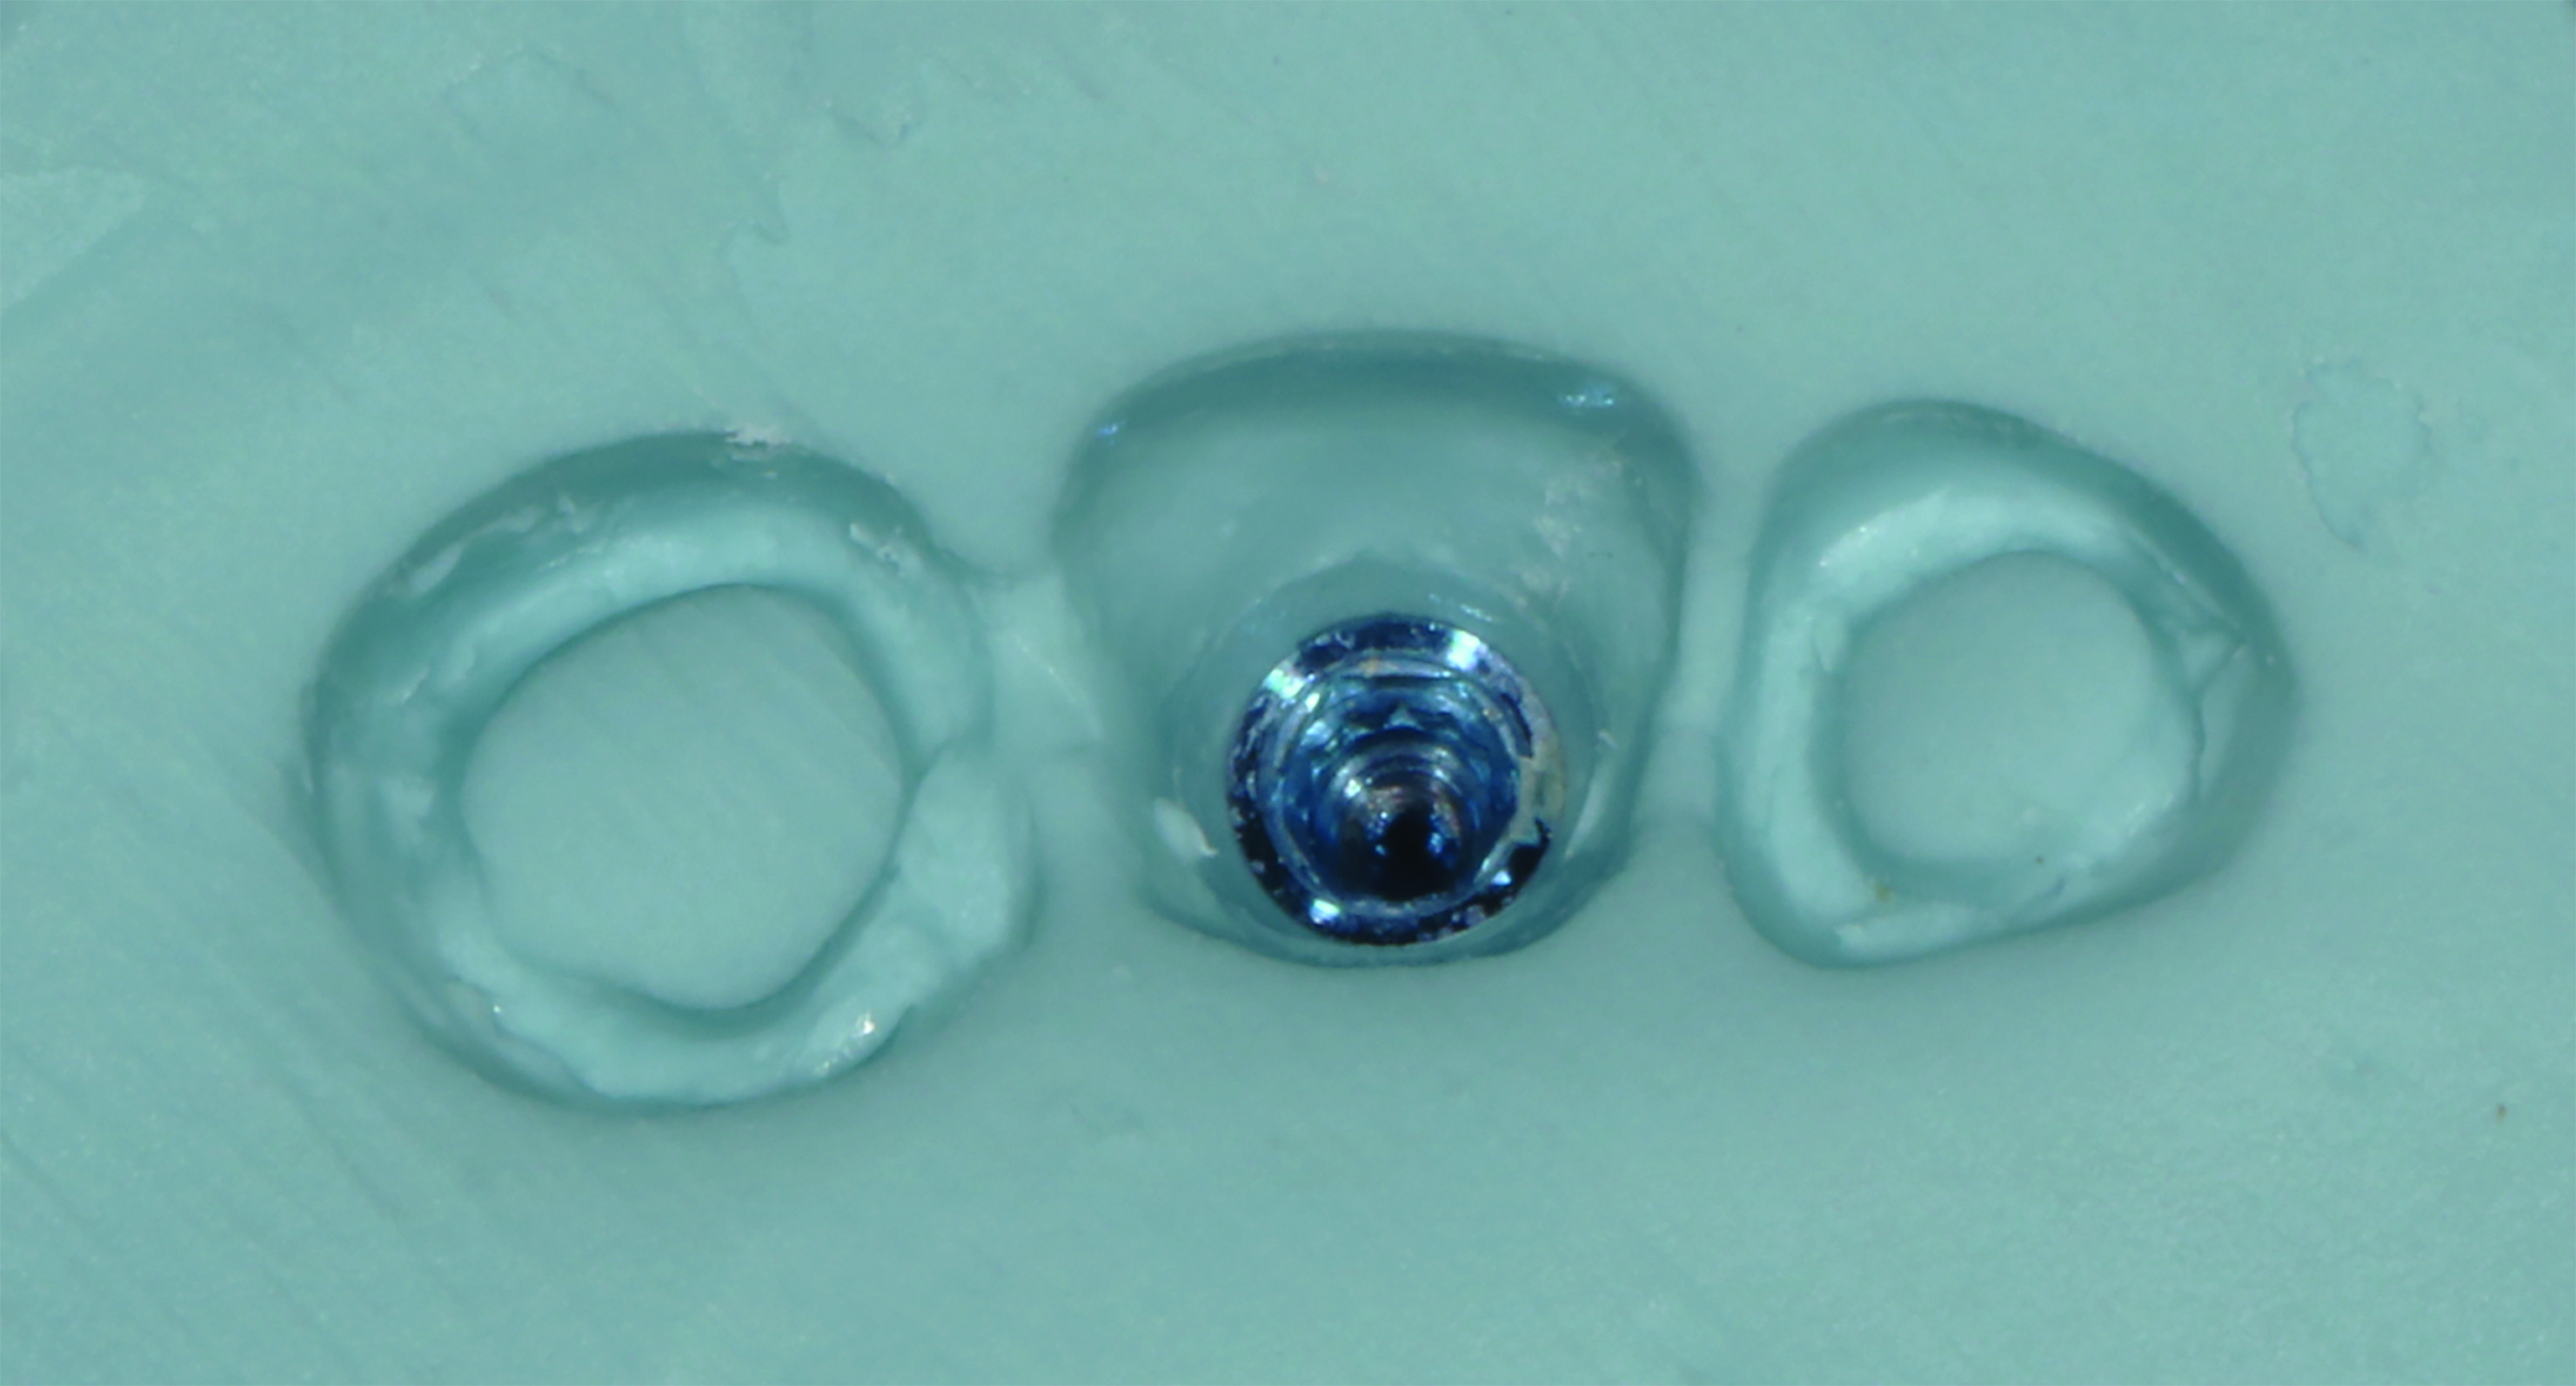

Fig 1. The patient’s initial presentation with healing abutments. (Surgical procedures performed by Mohammad Almogahwi, BDS, and prosthetic procedures performed by the author.)

Figure 1